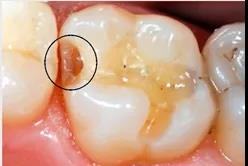

龋齿探测

龋齿探测仪检查:在龋齿探测仪的咬合面的图像上显示,近中合面存在低密度的阴影区。判断有邻面龋。